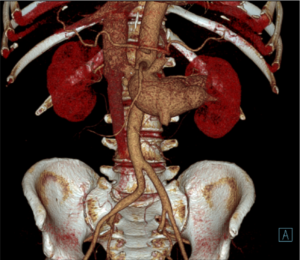

Под местной анестезией выполнено четыре пункции сосудов рук и ног (плечевые и бедренные артерии справа и слева) и выполнено уникальное эндоваскулярное протезирование брюшного отдела аорты стент-графтом от уровня почечных артерий и самих почечных артерий, таким образом исключив из кровотока патологический процесс – артериовенозное сообщение.

По данным контрольной ангиографии непосредственно после оперативного вмешательства: адекватное позиционирование стент-графтов, без признаков диссекций, нарушения целостности артериальных сосудов. Почечные артерии и верхняя брыжеечная артерия проходимы, почечная вена визуально уменьшилась до нормальных размеров.